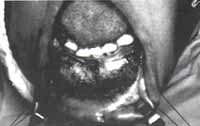

– Sutura de la cápsula quística a la mucosa oral, en toda la extensión de la herida quirúrgica. Fig. No. 6-7-8-9).

Fig. 6 Incisión de la mucosa vestibular de región canina izquierda a región premolar derecha.

Fig. 7 Obsérvese la exposición de la cortical externa expandida y adelgazada.

Fig. 8 Incisión de la cortical externa lo mismo que de la membrana quística. Se observa en el interior de la cavidad el canino incluido localizado en el borde inferior del maxilar y múltiples tabiques óseos a lo largo de la cavidad.

Fig. 9 Nótese mediante la sutura de la mucosa oral y la cápsula quística, la amplitud de la exposición del quiste.